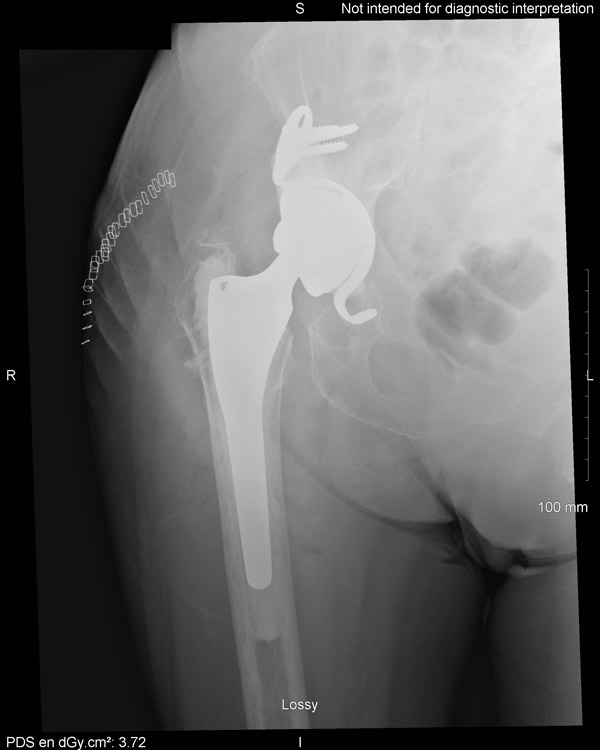

Per operative distal femur fracture requiring plate osteosynthesis

- Poor acetabular bone quality requiring the placement of a support ring (Kerboull cross)

Secondary displacement at one month

Surgical revision : Burch Schneider ring